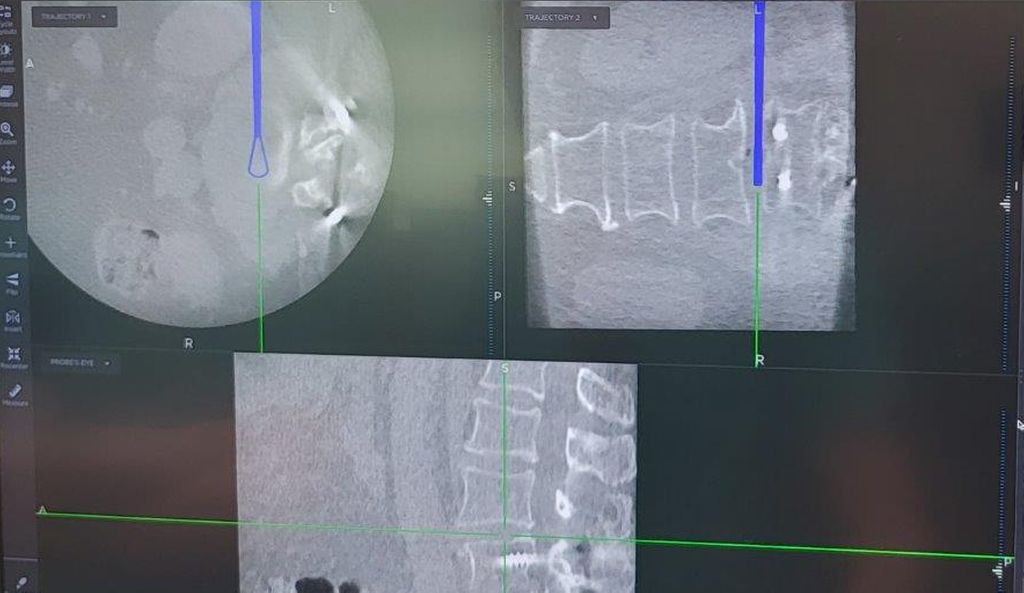

Navigierte Implantation eines „interbody device“ über lateralen Zugang (XLIF; „Xtreme lateral interbody fusion“). Bei der 79-jährigen Patienten kam es nach Fusion L4/5 vor mehr als 10 Jahren zu einer symptomatischen Anschlusssegmentdegeneration L3/4 mit Schmerzen im Dermatom L4 beidseits sowie zu Lumbago. Es erfolgte navigiert die Implantation eines Zugangs in Rechtsseitenlage. Intraoperativ wurde die Referenz am Beckenkamm platziert (Abb. 12) und mit intraoperativem CT (O-Arm) ein 3D-Datensatz gewonnen. Anhand dessen können Instrumente wie Küretten oder Raspatorium (Abb. 13) wie auch die Implantation des Cages selbst (Abb. 14) navigiert werden. Das postoperative Röntgen zeigt einen regelrechten Implantatsitz (Abb. 15).